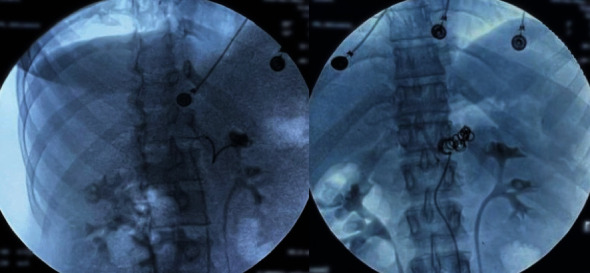

Iatrogenic aneurysms of the splenic artery constitute a rare yet potentially severe complication arising from diverse medical or surgical interventions. The clinical complexity and challenging management strategies associated with these aneurysms pose significant difficulties for clinicians. This circumstance is exemplified in our case report, detailing an iatrogenic aneurysm of the splenic artery that emerged secondary to a pancreatic fistula following a median pancreatectomy performed for a Frantz tumor. The intricate clinical presentation of this case underscores the considerable management challenges posed by such iatrogenic complications.